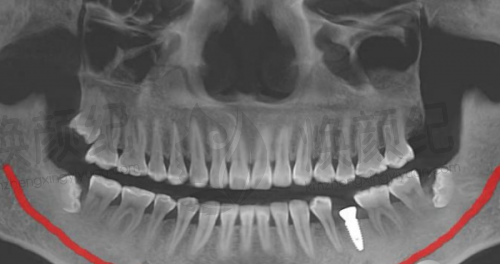

缺牙后选种植牙,特别多人都想参考真实实例,看看不同口腔条件下的治疗成效、修复过程和实际体验。营口团圆口腔肖宏亮医生深耕种植领域17年,接诊过各类缺牙病例,从单颗缺失到半口复杂种植都有丰富经验。下面分享3个不同类型的真实实例,从患者视角还原诊疗过程,给有需求的朋友提供参考,所有实例均经患者同意,无夸张表述。